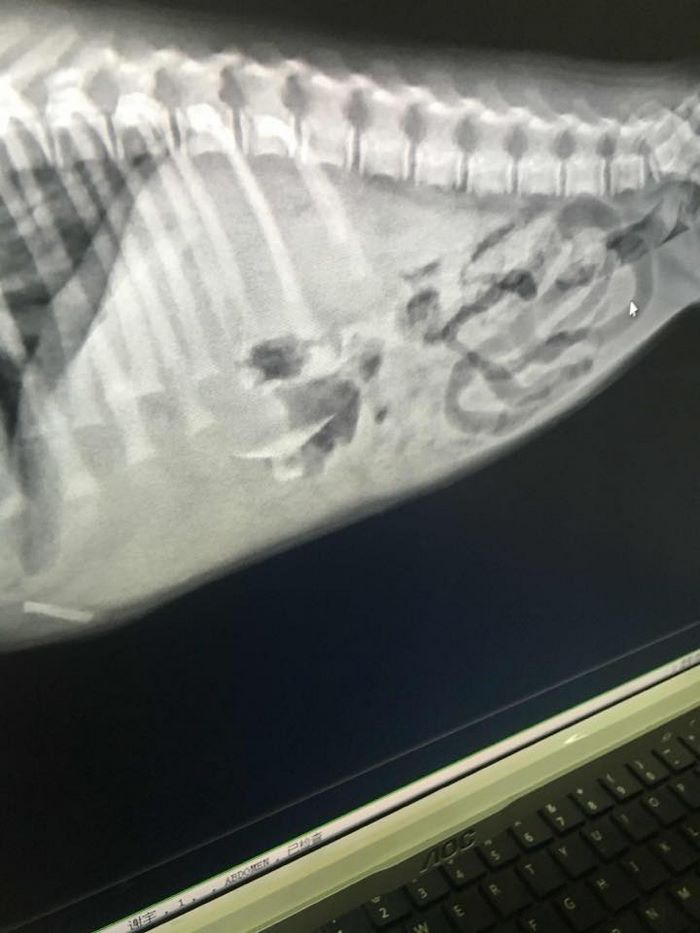

She also managed to swallow a plastic window sucker and had to undergo a surgery